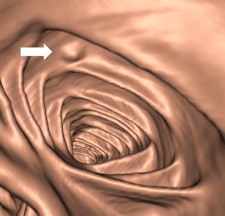

Along with his colleague Dr. Stefaan Gryspeerdt, Lefere has addressed CTC's potential pitfalls in a comprehensive paper published online January 4 in Insights into Imaging. Their top tips are to perform state-of-the-art CTC (preparation based on fecal tagging, along with colonic distension with CO2 plus injector, dual positioning, and smooth muscle relaxation), remember the general principles of interpretation, and take special care when examining the rectum and caecum.